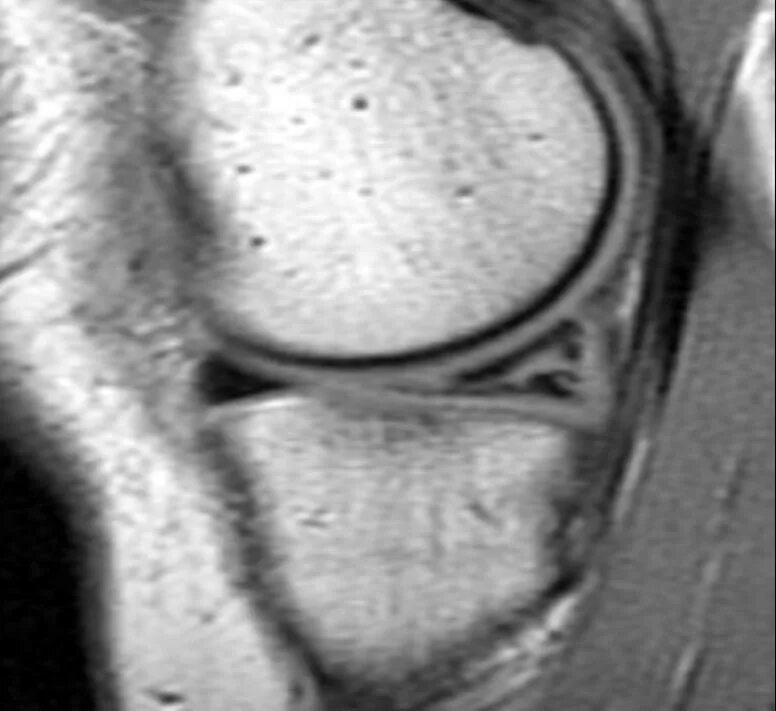

Задний рог внутреннего мениска 2 степени